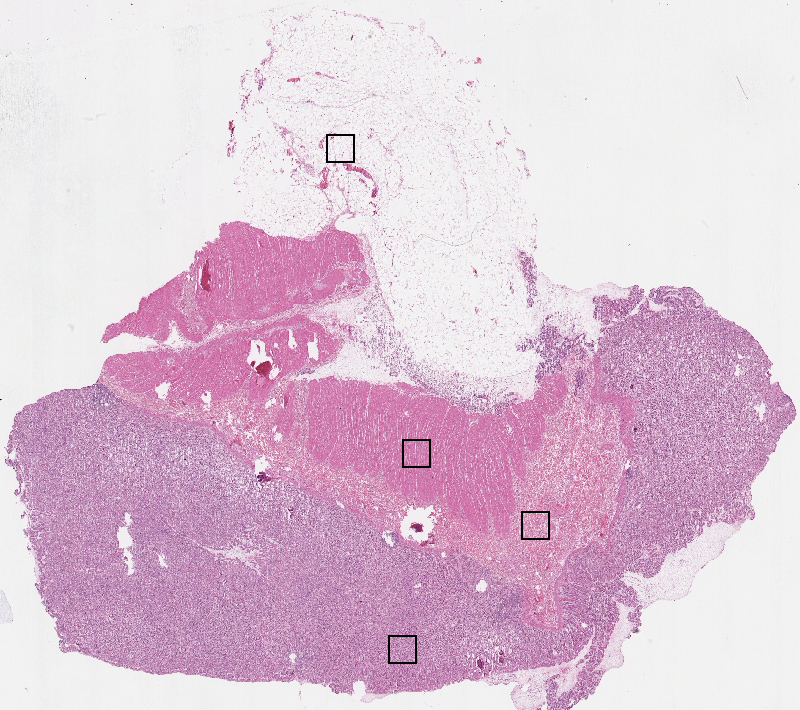

Cell types%

Glandular cells:

50

Smooth muscle cells:

15

Other cell types:

35